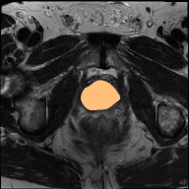

4.3 Qualitative Results of DSPIF

Some qualitative results of the proposed DSPIF are shown in Fig. 3. Both USPIF and LSPIF generate images with diverse appearances while preserving the same topological structure as the original image. Inheriting from the property of connected filters, the proposed DSPIF does not create any new contours. It is also noteworthy that monotonically increasing contrast change map pixels with the same graylevel to the same output graylevel. Differently, the output of DSPIF does not only depend on the input graylevel, but also the image structure. As shown in the first row of Fig. 3, for similar input graylevels on different pixels, USPIF may output very different graylevels on these pixels. Yet, the topological image structure is preserved.

Some qualitative segmentation results on the three datasets are shown in Fig. 4, where we can observe that the proposed DSPIF achieves accurate segmentation results.